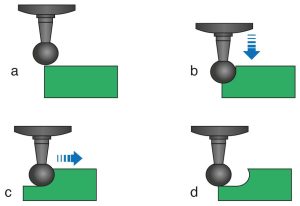

The occlusal rest seat can be prepared with rond burs, round-tipped or progressively narrower diamond burs (Fig. 10-34). When using a round diamond bur, care must be taken not to create an undercut in the rest seat (Figure 10-35). Round-tipped and progressively narrower burs allow for preparation without creating an undercut (Fig. 10-36).

a) Round bur positioned above the enamel surface

b) Round bur advanced vertically

c) Round bur advanced horizontally

d) The undercut when the bur is removed